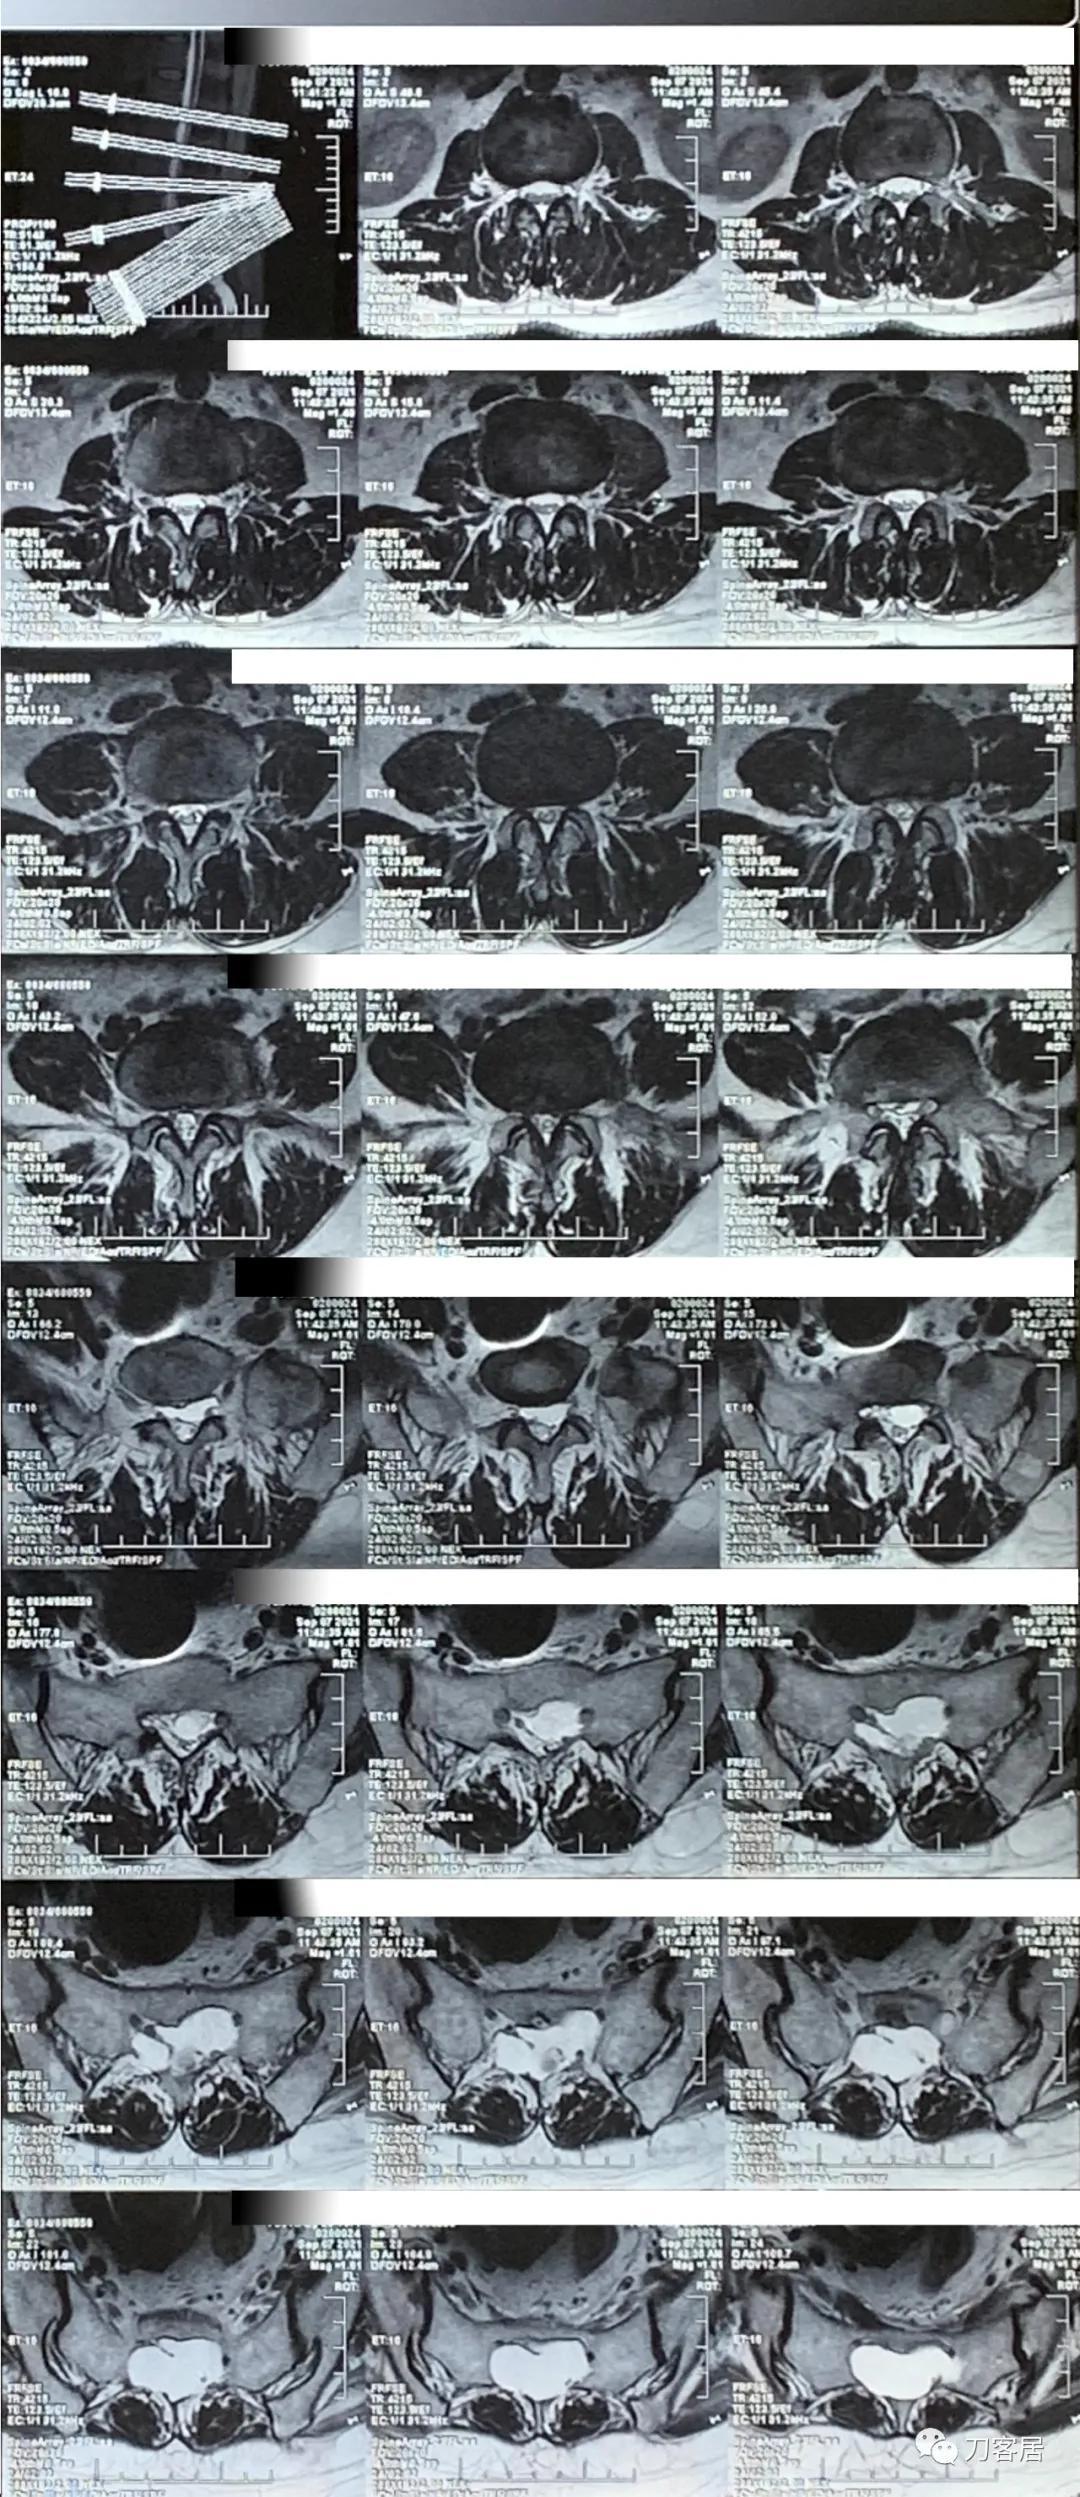

图5. 20210907西安国际医学中心腰椎MRI横截面,提示骶管囊肿较大,且宽。

图6. 20210907西安国际医学中心腰椎MRI横截面扫描,提示腰3-5椎间盘突出及椎管狭窄均不严重。